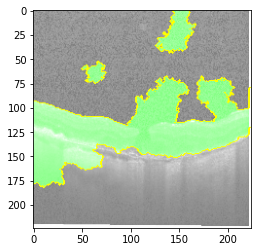

Original Image

Explanation B

Explanation C

Explanation D

GradCAM

Fig 6, 7, 8 and 9 depicts the visualization of correct predictions by our proposed CNN model where fig 6 is class CNV, fig 8 is class DME, fig 7 is DRUSEN and finally, fig 9 is NORMAL. Here the first photo in every class is the original image. The LIME map of our suggested model’s prediction is shown in image B whereas in image C the positive region is highlighted in specific sections on the original image. For Image D we have increased the number of features from 5 to 10 thus more regions have been predicted as the positive region which is highlighted in green. After increasing the features from 5 to 10, some of the regions are predicted wrongly. The red regions represent the output of incorrect prediction. The following image represents the Grad-CAM heatmap highlighting the regions with our model’s prediction.